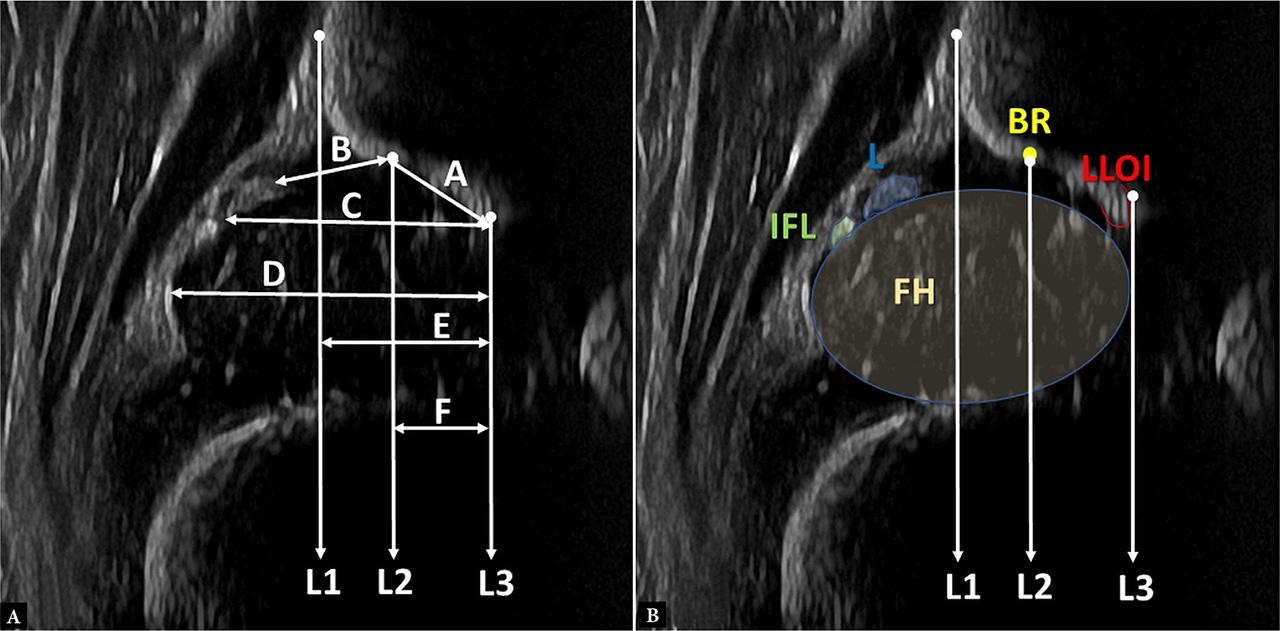

Within each image, three lines and six distances were drawn and calculated, respectively (Fig. 1):

L1: “base line”(7).

L2 and L3: lines drawn parallel to L1. L2 begins from the “bony rim” (most lateral point of the concavity of the bony part of the acetabulum) and L3 begins from the medial border of the “lower limb of the os ilium”.

Distance A (A): distance from the medial border of the “lower limb of the os ilium”, to the “bony rim”, measured tangential to the bony part of the acetabular roof.

Distance B (B): distance from the middle, medial border of the labrum to the “bony rim”.

Distance C (C): distance from L3 to the outer border of the labrum, which is a measure of the depth of the acetabular roof (including the fibrocartilaginous labrum).

Distance D (D): distance from L3 to the outermost border of the femoral head, which is a reproducible measure of the width of the femoral head.

Distance E (E): distance from L3 to L1, which is a measure of the width of the part of the femoral head that lies medial to the silhouette of the os ilium.

Distance F (F): width of the “bony roof”, defined as the width of the bony part of the acetabulum.

A. Demonstration of the lines and measurements which were evaluated. B. Schematic representation of major anatomical landmarks. FH – femoral head, L – labrum, IFL – ischiofemoral ligament, BR – bony rim; LLOI – lower limb of the os ilium